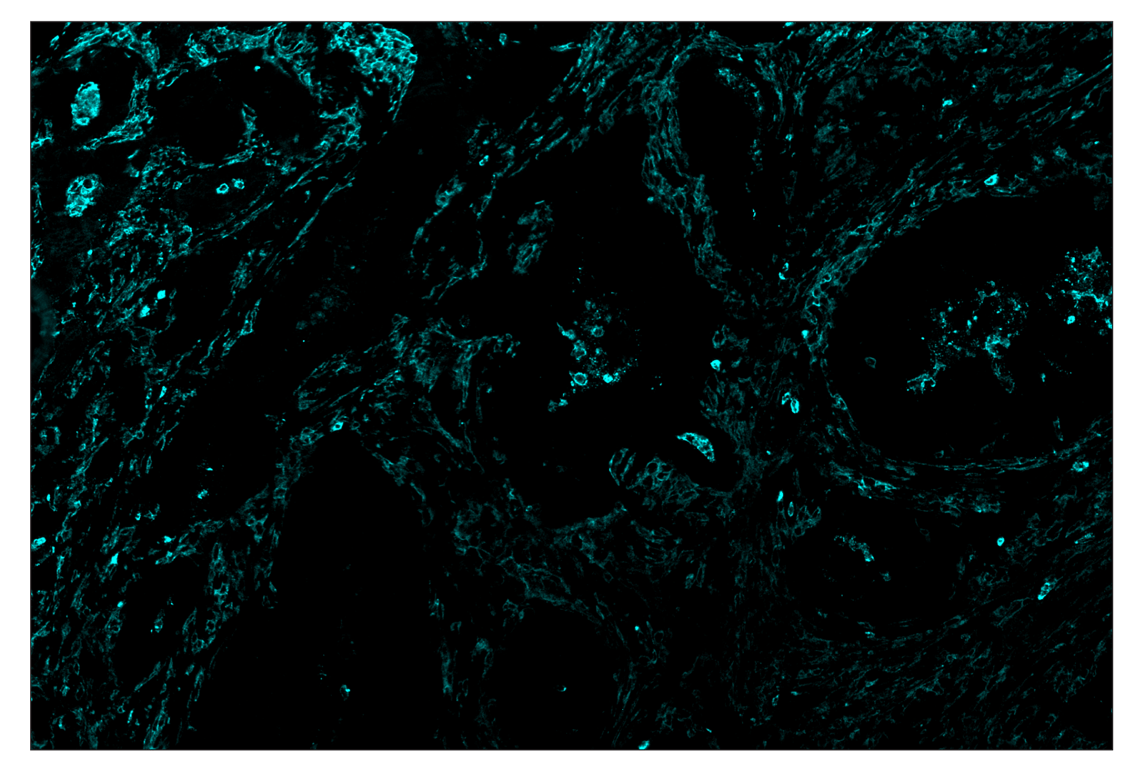

SignalStar™ immunohistochemical analysis of paraffin-embedded human colorectal adenocarcinoma using CD11b/ITGAM (D6X1N) & CO-0037-750 SignalStar™ Oligo-Antibody Pair #67799 (cyan). All fluorophores have been assigned a pseudocolor, as indicated. Staining was performed on the BOND RX autostainer by Leica Biosystems.

Immunohistochemistry Image 5: CD11b/ITGAM (D6X1N) & CO-0037-647 SignalStar<sup>™</sup> Oligo-Antibody Pair